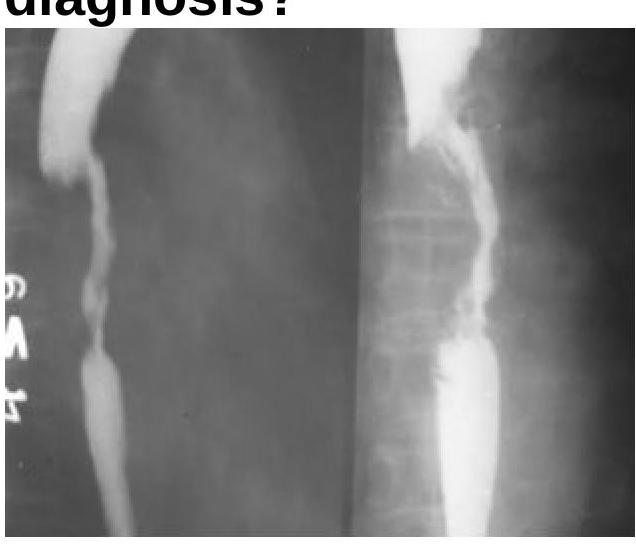

The Barium Swallow examination shows a filling defect in the esophagus. What is the most probable diagnosis?

Explanation: ***Esophageal Carcinoma*** - A filling defect on a barium swallow study, especially with irregular borders and luminal narrowing, is highly suggestive of an **esophageal carcinoma**. - The image appears to show an **irregular, obstructing lesion** that displaces the barium column, characteristic of a mass. *Esophageal Ring* - An esophageal ring, such as a **Schatzki ring**, typically presents as a thin, circumferential narrowing of the distal esophagus, forming a smooth, shelf-like indentation, which is not seen here. - Esophageal rings usually cause **intermittent dysphagia** to solids but do not present as a large, irregular filling defect. *Esophageal Tear* - An esophageal tear (e.g., **Mallory-Weiss tear**) is a mucosal laceration that would present with **hematemesis** and would typically appear as a linear defect or streak on a barium swallow if visible, not a filling defect. - A tear is not usually associated with a persistent mass effect or irregular luminal obstruction seen in the image. *Achalasia Cardia* - **Achalasia** is characterized by the failure of the lower esophageal sphincter to relax and **absent peristalsis** in the esophageal body, leading to a classic "bird's beak" or "rat tail" appearance on barium swallow due to distal narrowing and proximal dilation. - While it causes luminal narrowing, it does not typically present as an irregular filling defect within the lumen, but rather as a smooth tapering of the distal esophagus.